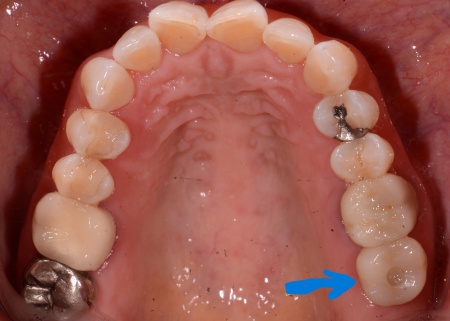

治療後

| 行った治療内容 | 診断内容を丁寧にお伝えしたうえで、抜歯後に歯を補うため、以下2つの治療方法を提案しました。 ①取り外し式の入れ歯 メリット:外科的な処置を行わずに治療でき、比較的短期間で作ることが可能 デメリット:取り外しが必要で、装着したときに違和感を覚えることがある ②あごの骨に人工の歯根を埋め込み、その上に人工の歯を取り付けるインプラント治療 メリット:固定式のためご自身の歯に近い感覚で噛むことができる デメリット:外科手術が必要で自由診療となり、治療期間も比較的長くなる それぞれのメリット・デメリットをお伝えしたところ、患者様は②のインプラント治療を希望されました。併せて治療の流れや外科処置に伴うリスクについてもしっかりとお伝えし、左上奥歯の抜歯とインプラント治療に同意いただきました。 まず、左上の奥歯を抜くと同時にインプラントを埋め込む抜歯即時埋入を行います。 これは、歯を抜いた直後のあごの骨に人工歯根を埋め込む治療方法です。 事前のレントゲン検査で骨の状態を確認し、インプラントを埋め込む位置や角度を慎重に検討したうえで処置しました。 その後、歯ぐきやあごの骨が回復するまで一定期間待ち、インプラントが骨としっかり結合しているかを確認しました。 問題がないことを確認したうえで歯の型取りを行い、インプラントの上に装着する人工歯を作製しています。 最後に完成した人工歯を取り付け、噛み合わせに問題がないかなどを確認し治療を終了しました。 |